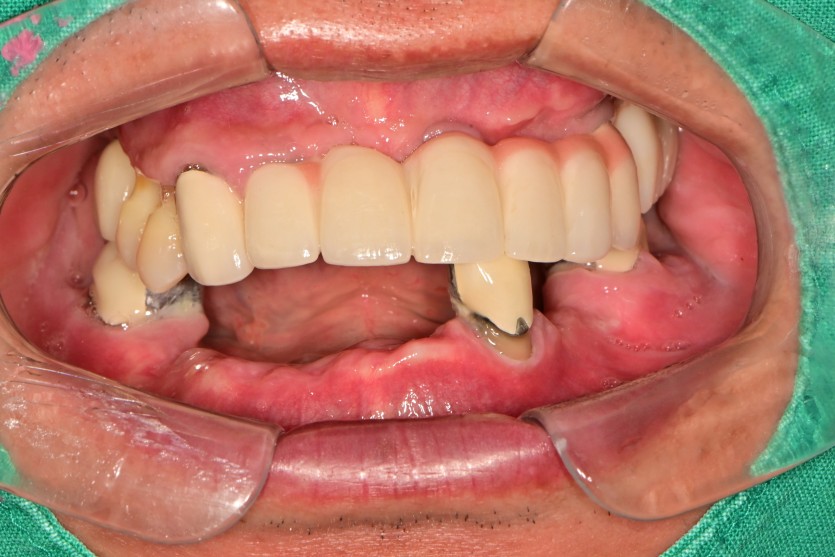

만 56세 하악 전체 임플란트 증례(상악 일부)

하악 전체 임플란트 증례입니다.

11개의 임플란트로 완성하였습니다.